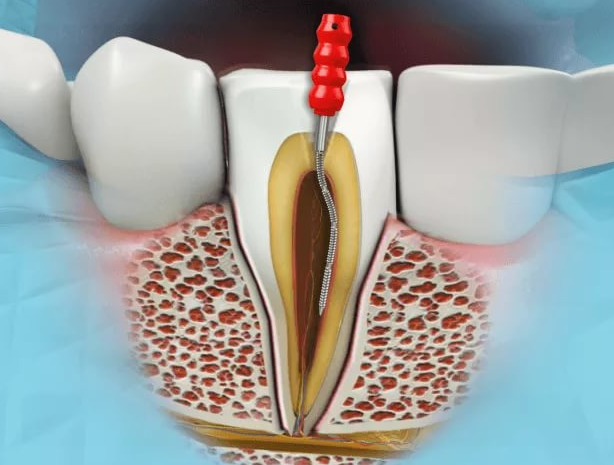

Во внутреннем пространстве зуба находится пульпарная камера и каналы корня зуба, содержащие пульпу — сложную биологическую ткань. Многие называют пульпу зуба «нервом». Действительно, пульпа содержит нервы, но в ней есть также и артерии, вены, сосуды лимфы, клетки и соединительная ткань.

Во внутреннем пространстве зуба находится пульпарная камера и каналы корня зуба, содержащие пульпу — сложную биологическую ткань. Многие называют пульпу зуба «нервом». Действительно, пульпа содержит нервы, но в ней есть также и артерии, вены, сосуды лимфы, клетки и соединительная ткань.

Инфицирование пульпы приводит к ее воспалению (пульпит) и, в последующем, к гибели. Финалом воспаления пульпы является воспаление тканей периодонта в области верхушки корня (периодонтит). Свидетельством воспаления может быть то, что зуб неоднократно болел или продолжает болеть; десна вблизи зуба стала чувствительной и/или опухла.

Также пульпа может погибнуть в результате хронической инфекции или травмы тихо и незаметно, не вызывая боли и неприятных ощущений, и тогда зубы, нуждающиеся в лечении, могут оставаться незамеченными даже в течение нескольких лет. В этих случаях врачу удается обнаружить такие зубы с помощью рентгеновского исследования.

Воспаление и, тем более, гибель пульпы требуют сложного эндодонтического лечения или, как говорят проще, — «лечения каналов».

Воспаление и, тем более, гибель пульпы требуют сложного эндодонтического лечения или, как говорят проще, — «лечения каналов».

Главная цель эндодонтического лечения — очистка от микроорганизмов и продуктов их жизнедеятельности внутренних полостей зуба и тщательное заполнение их пломбировочным материалом с последующим восстановлением формы зуба.

Лечение ведется под анестезией без использования препаратов типа мышьяка. Все этапы обработки и пломбирования каналов проводится под радиовизиографическим контролем. Лечение требует, как правило, 2-3 посещения по 1-1,5 часа каждое.

Этапы лечения:

- Препарирование полости, создание доступа к корневым каналам и удаление воспаленной пульпы, продуктов ее распада.

- Поиск всех каналов зуба (их количество различно в разных зубах и может достигать 5).

- Определение длины каналов с помощью апекслокатора или радиовизиографическим методом.

- Этап механической обработки каналов вручную и машинным способом при помощи эндодонтических файлов, цель которой — очистка и придание оптимальной для последующего пломбирования формы. В процессе работы каналы периодически промываются антисептическим раствором с целью дезинфекции и для удаления появившихся в процессе работы отходов. Для усиления бактерицидного эффекта используется ультразвук.

- Пломбирование каналов зуба. Иногда канал заполняется пломбировочным материалом сразу после очистки канала. В других случаях врач может сделать между этими этапами интервал в несколько дней. В этом случае ставится временная пломба, чтобы за это время в канал не попала инфекция. После герметизации каналов и радиовизиографического контроля качества пломбирования лечение каналов можно считать завершенным.

- Реставрация зуба. После окончания лечения каналов для нормального функционирования зуба требуется его восстановление. Во многих случаях в процессе лечения каналов зуб лишается довольно значительных объемов твердых тканей. Зубы в таком состоянии уже не такие прочные, какими они были когда-то, и врач определяет, каким способом можно восстановить зуб — при помощи вкладки, ортопедической коронки, или коронки в комбинации со штифтом. Конечно, врач объяснит вам, какой из этих методов и почему больше подходит в Вашем случае.